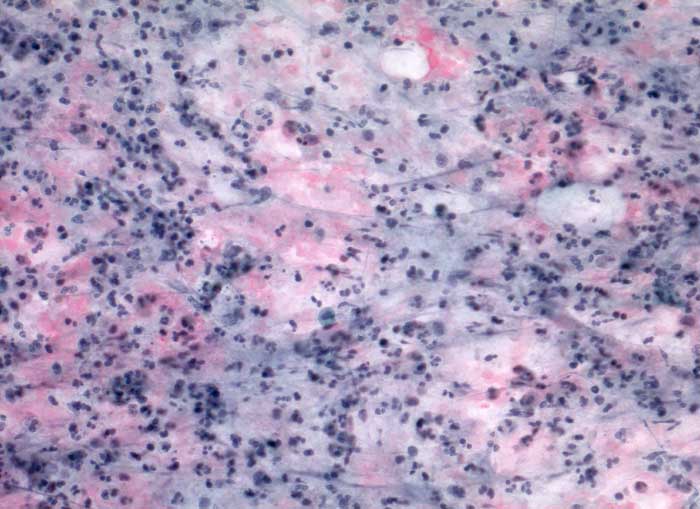

akute Sialadenitis

Entzündung / Reparatur

Parotis

Feinnadelpunktion Parotis: Im Hintergrund amorphes eiweissartiges Material. Massenhaft neutrophile Granulozyten und Makrophagen.

Akute Entzündung der Speicheldrüse DD: maligner Tumor

Keine histologische Untersuchung notwendig

Zytologie

200